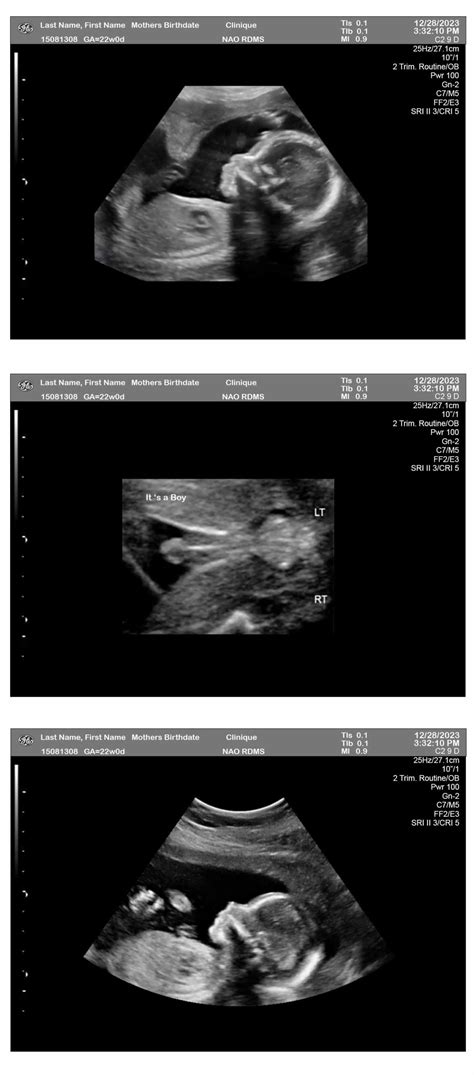

In the next image, you can see a distinctive Fourteen Week Ultrasound ikon:

Fourteen Week Ultrasound Image

This image provides a glimpse into the detailed views that can be get during this crucial scan, highlighting the baby's developing features and overall health.